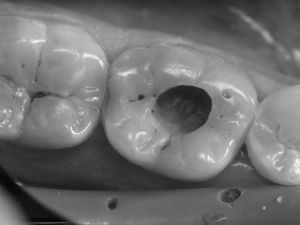

На фото дірка в зубі, як результат руйнівної дії карієсу